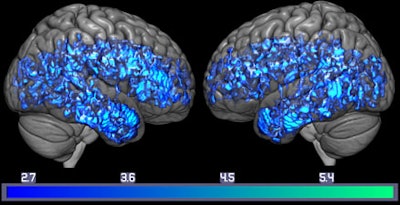

PET brain image shows decrease of serotonin transporters (blue) in the whole mild cognitive impairment group, compared with the whole healthy control group. Image credit: Gwenn Smith lab.Subjects with mild cognitive impairment showed up to 38% less of the serotonin transporter in the brain, compared with the age-matched controls. In addition, when Smith and colleagues compared the imaging results with memory tests, they found that lower serotonin transporter levels correlated with lower test scores. For example, subjects with mild cognitive impairment had 37% lower verbal memory scores and 18% lower levels of the serotonin transporter in the brain's hippocampus, compared with healthy controls.